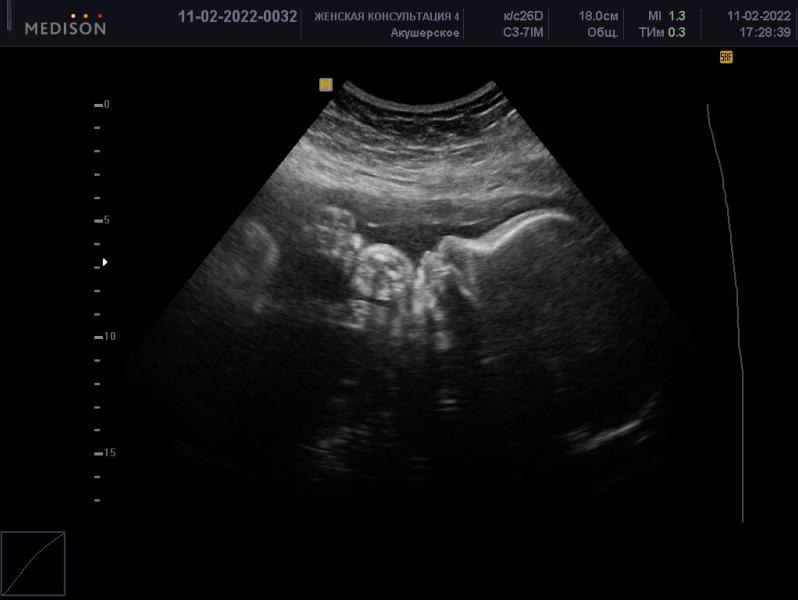

Только на 3 скрининге малыш надув губки показался в профиль 🤪

До этого закрывал лицо и руками и ногами, зато писюн показал на 11 недели))

У нас постоянно руки были рядом с головой, но лицо не закрывал… до момента 3 скрининга на 31 неделе, когда я очень хотела 3д фотографию лица😃 тут он даже профиль нормальный не показал, голова была немного отвернута от датчика😀

Так что мы смогли сфотографировать только ножку) ручку ещё показали и все)